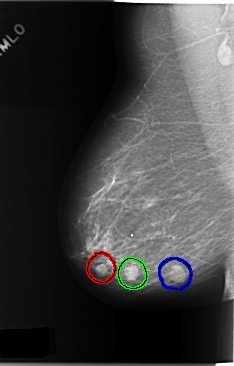

C_0174_1.RIGHT_MLO

RIGHT_MLO LINES 5856 PIXELS_PER_LINE 3744 BITS_PER_PIXEL 12 RESOLUTION 50 OVERLAY

FILE: C_0174_1.RIGHT_MLO.OVERLAY

TOTAL_ABNORMALITIES 3

ABNORMALITY 1

LESION_TYPE MASS SHAPE OVAL MARGINS CIRCUMSCRIBED

ASSESSMENT 4

SUBTLETY 5

PATHOLOGY BENIGN

ABNORMALITY 2

LESION_TYPE MASS SHAPE OVAL MARGINS MICROLOBULATED

PATHOLOGY MALIGNANT

ABNORMALITY 3